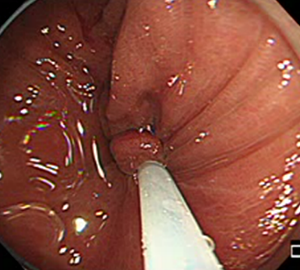

内視鏡的粘膜切除術(EMR)

外来にて切除することの出来ない、比較的大きめの大腸ポリープや平坦な病変などの切除の際に行います。

![]() |

|

| 1:ポリープを見つけ、NBI併用拡大観察をした後、 | 2:ポリープ直下の粘膜下層に局注液を注入し盛り上げます。 | |

| 3:ポリープをスネアに通し、周囲の正常粘膜を入れて病変を絞扼 | 4:電気を流してして切除します。 | |